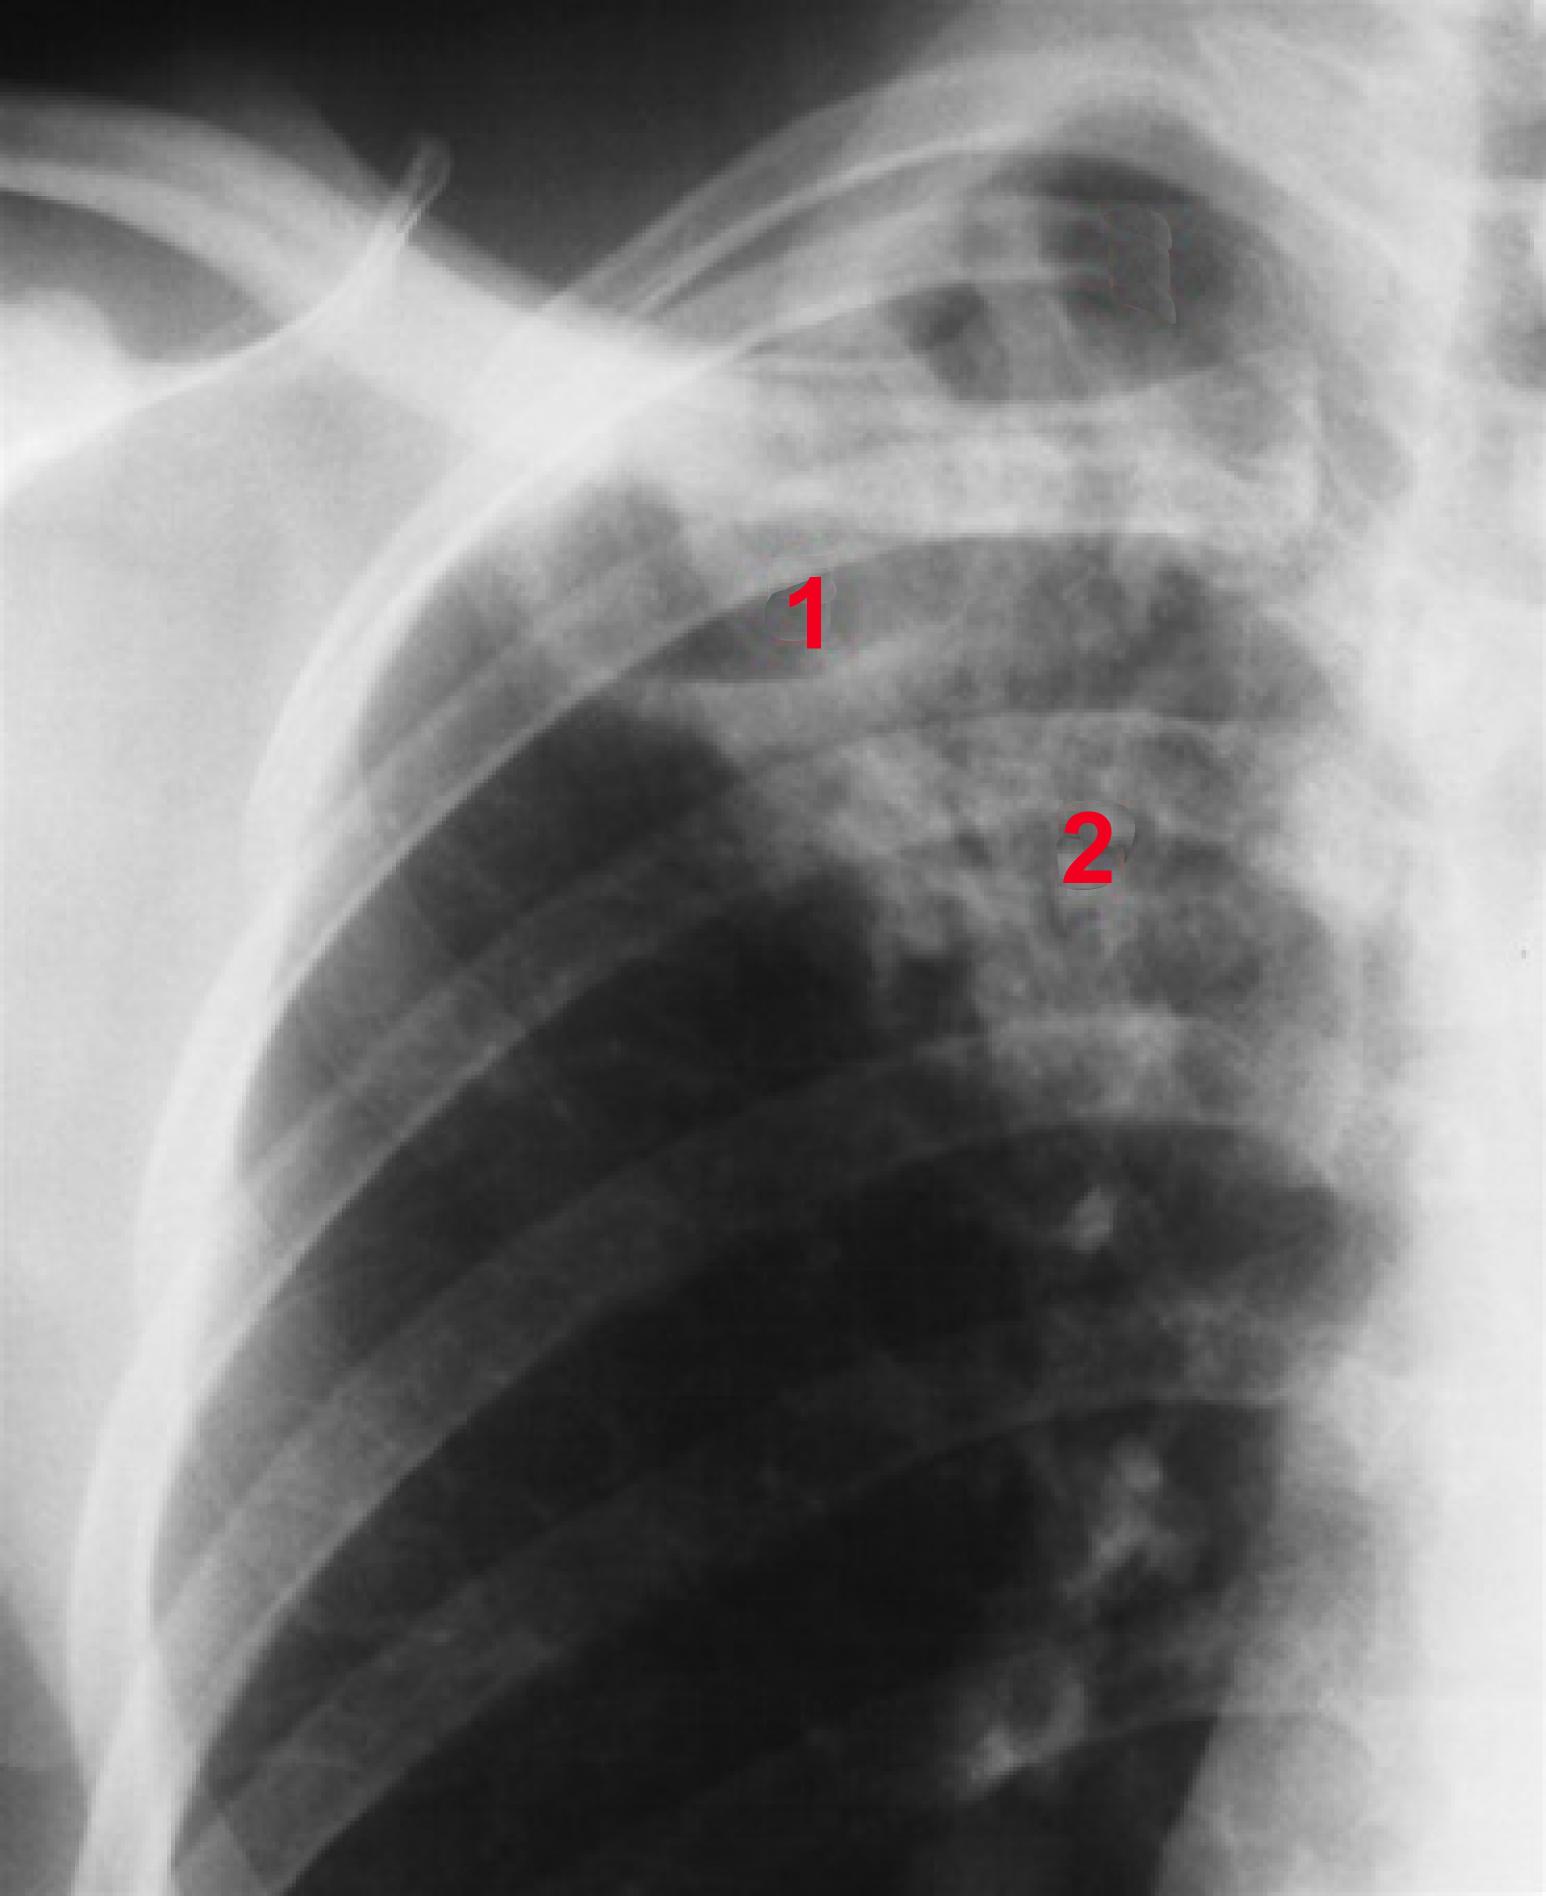

Billedet viser:

1. Kavitet i højre overlap uden væskespejl

2. Infiltrative forandringer (fortættet lungevæv)